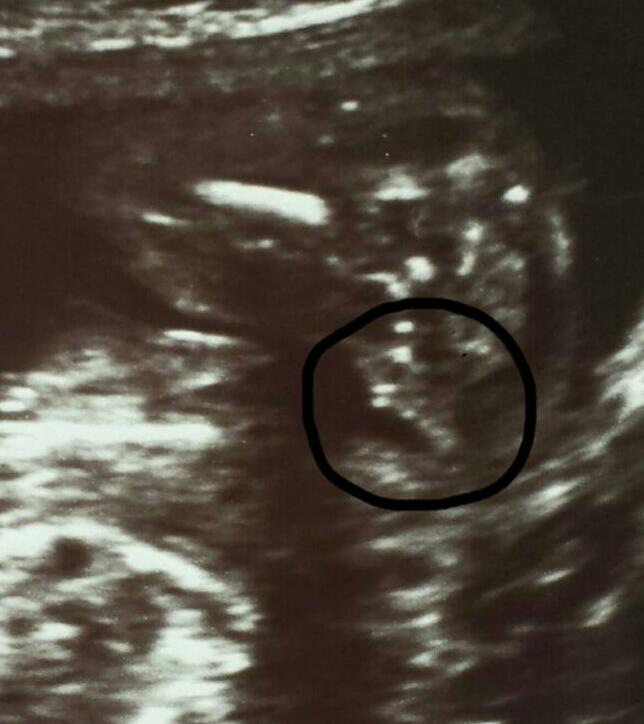

20 weeks. This is the only angle available :)Attachment 24751

I'm not sure what I'm looking at here, but I don't know if the gender is the thing you've put a ring around. I think the gender (girl) is higher up in the picture, but I'm not sure.